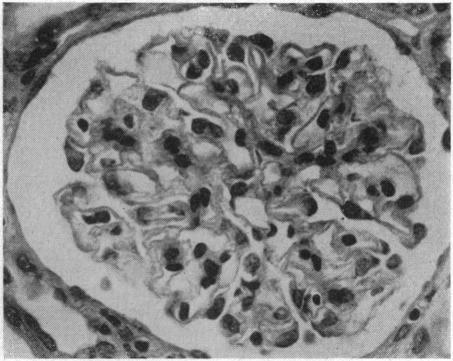

Cell and tissue damage through antigen-antibody complexes.

Calif Med. 1969 Aug;111(2):99-112.